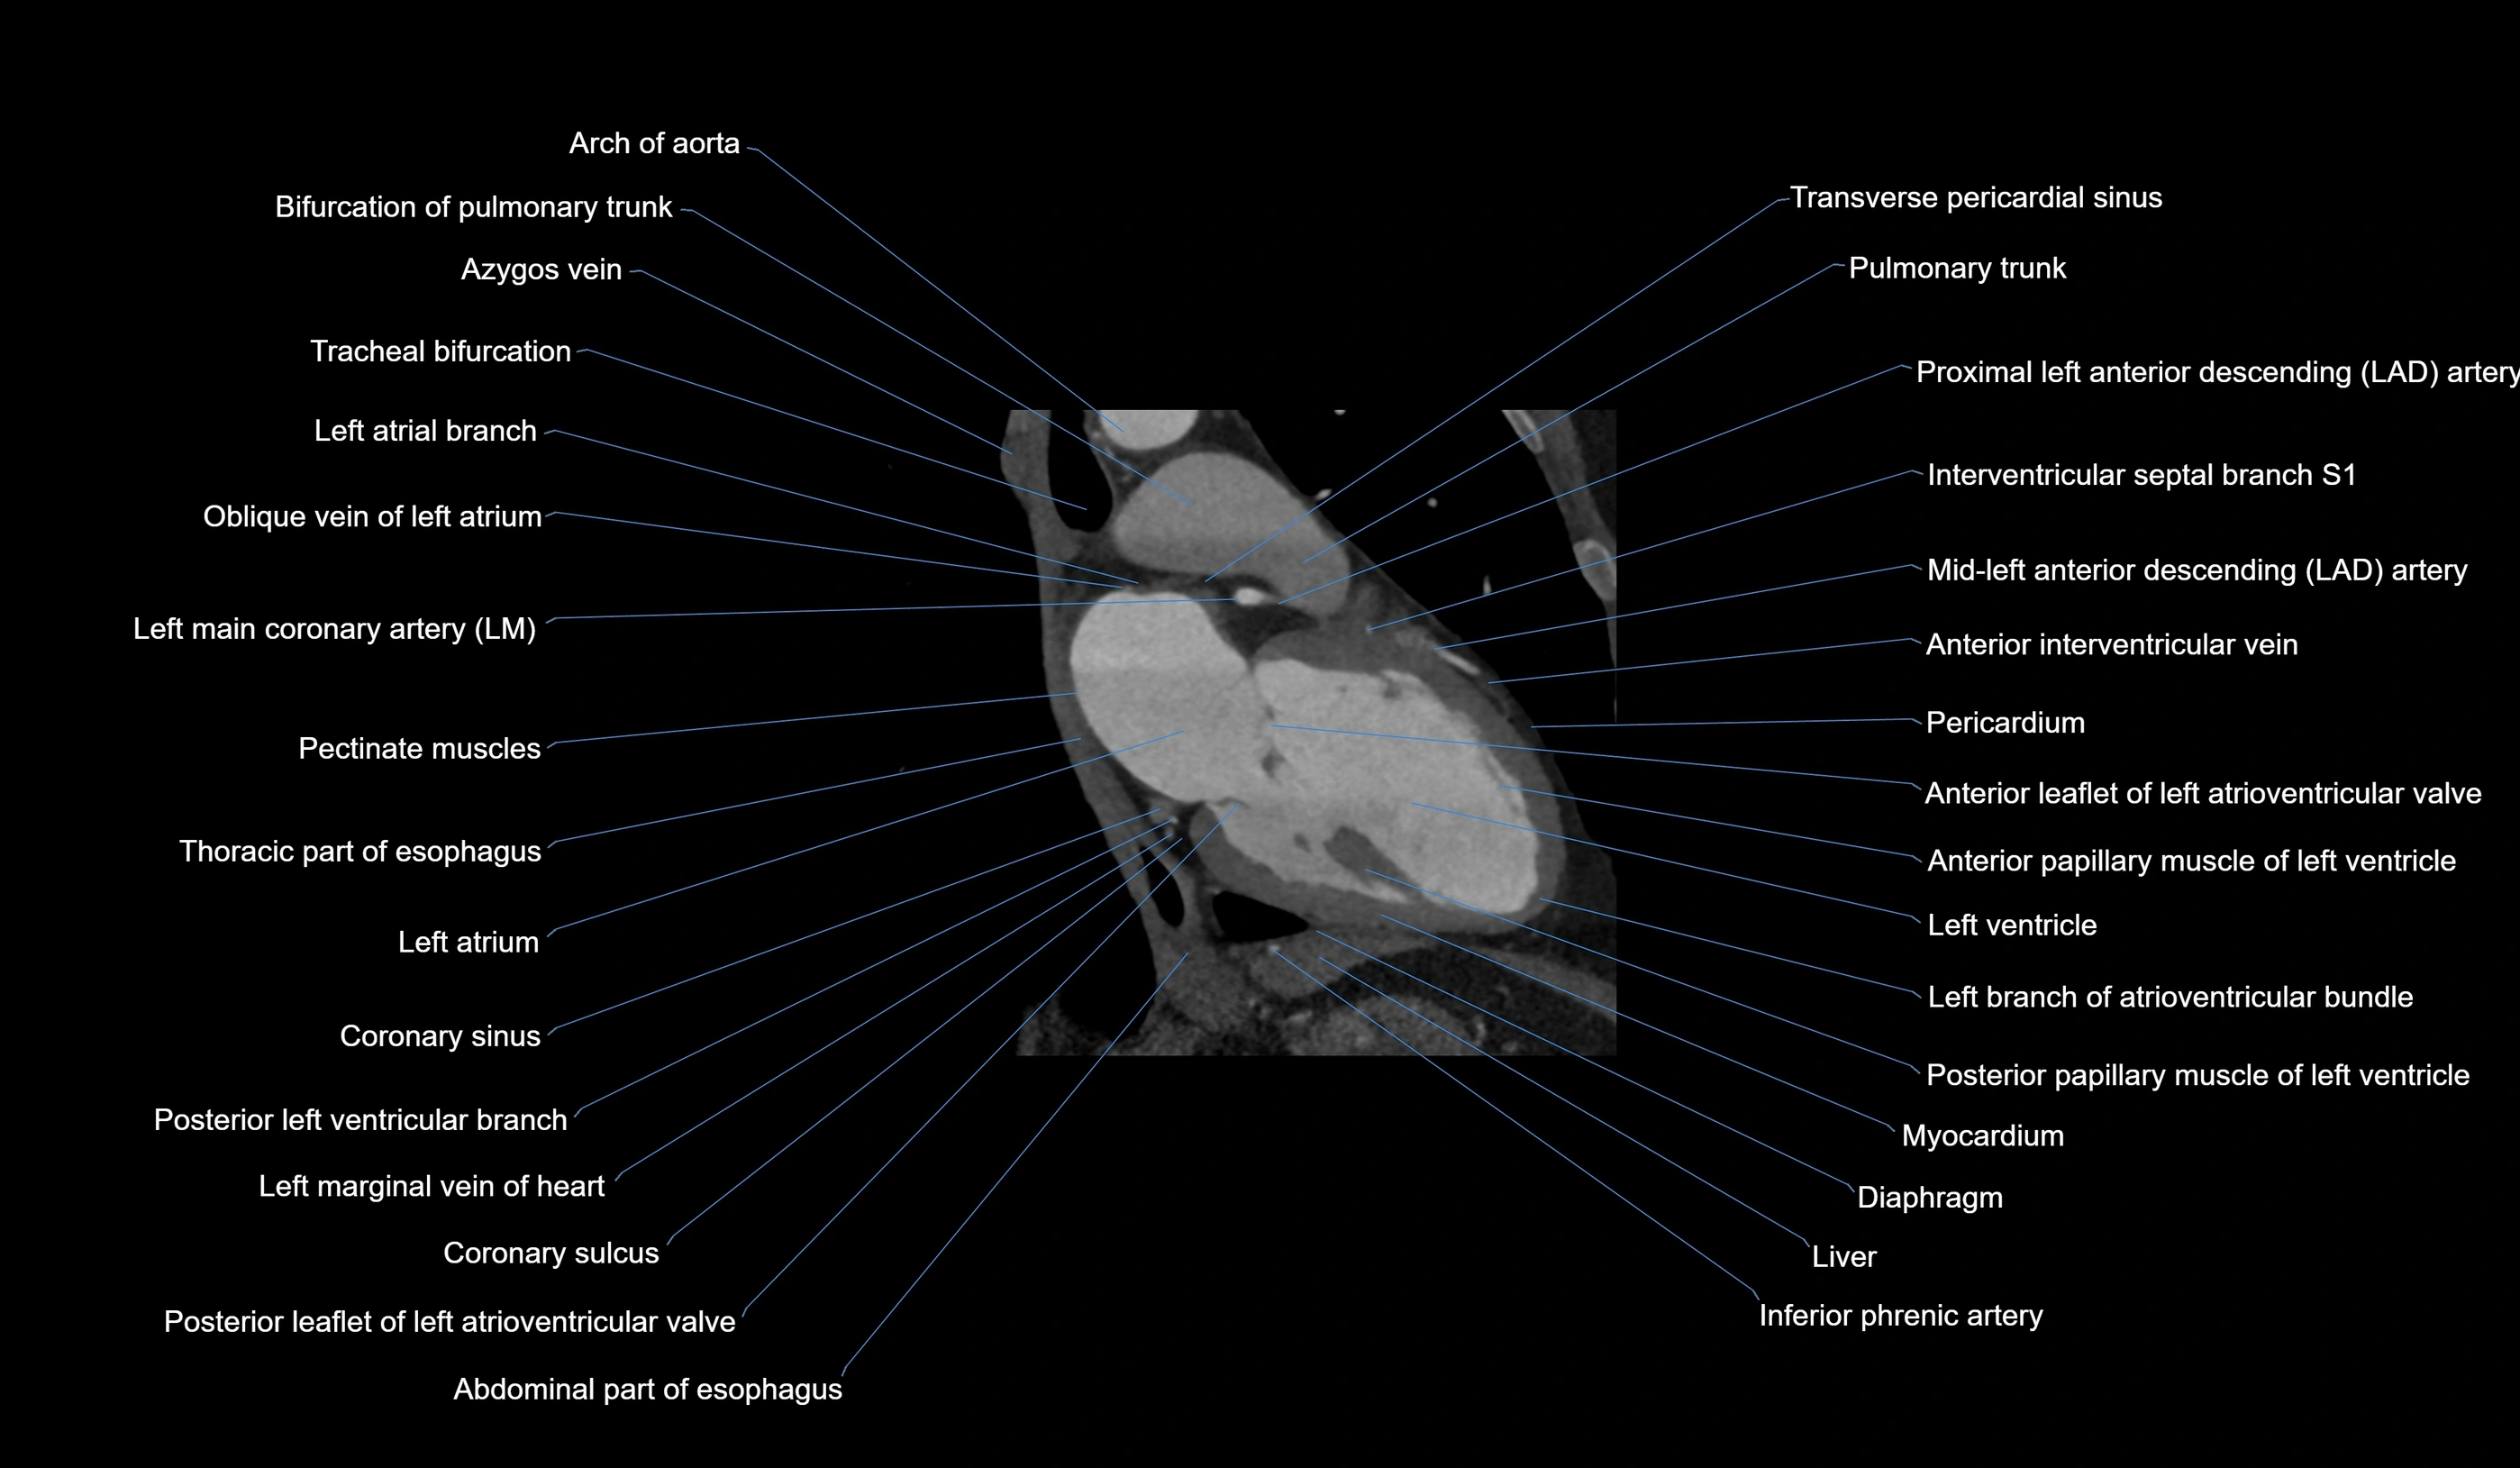

CT images